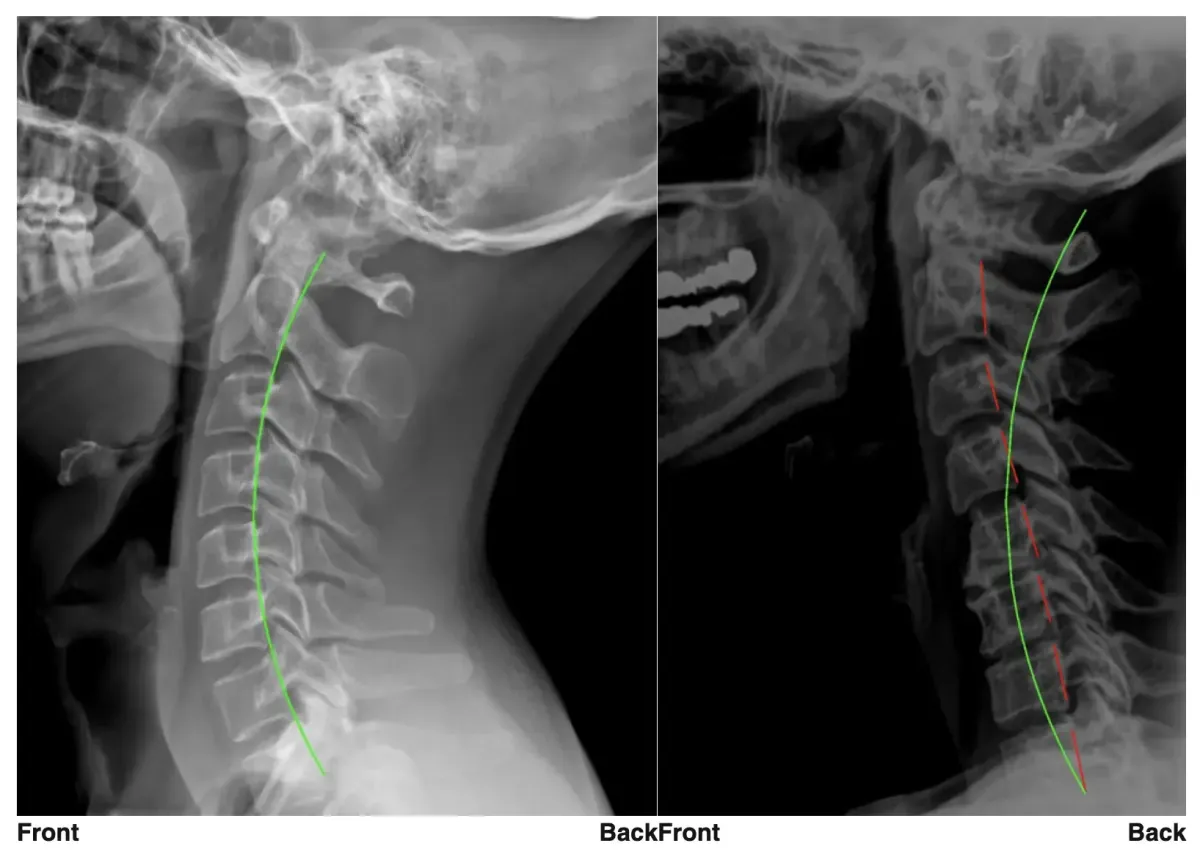

Precise X-Ray Reports

We use state-of-the-art technology from PostureRay to visualize your digital x-rays to measure spinal alignment and determine exactly what type of care is right for you.